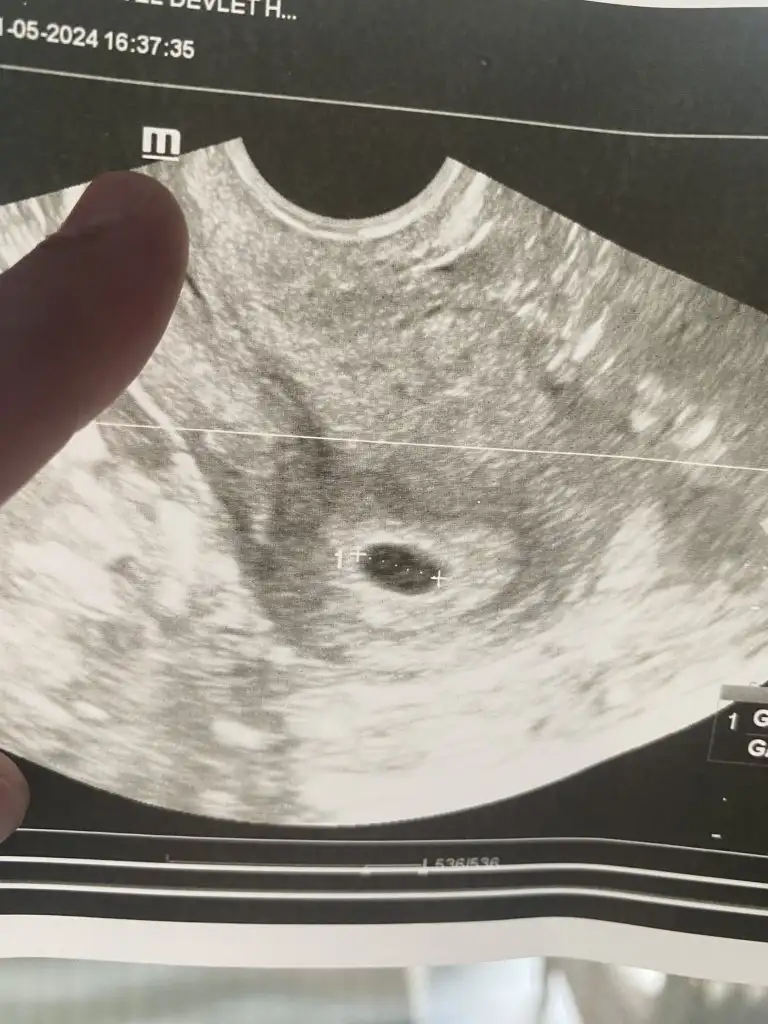

Hayırlı olsun çok sevindim sizin adınıza. Kaçıncı haftadasınız tam olarakEki Görüntüle 3435809 Keseyi dün mecbur alttan görmek zorunda kaldık. Tekrar kan verdim sonucum 4048 çıktı, karından muayyene edildiğinde göremedik keseyi. Doktorda mecbur alttan muayene etmeliyiz dedi ve çok şükür keseyi gördük![]()

Maşallah canım inşallah bize de nasip olur görmekEki Görüntüle 3435809 Keseyi dün mecbur alttan görmek zorunda kaldık. Tekrar kan verdim sonucum 4048 çıktı, karından muayyene edildiğinde göremedik keseyi. Doktorda mecbur alttan muayene etmeliyiz dedi ve çok şükür keseyi gördük![]()